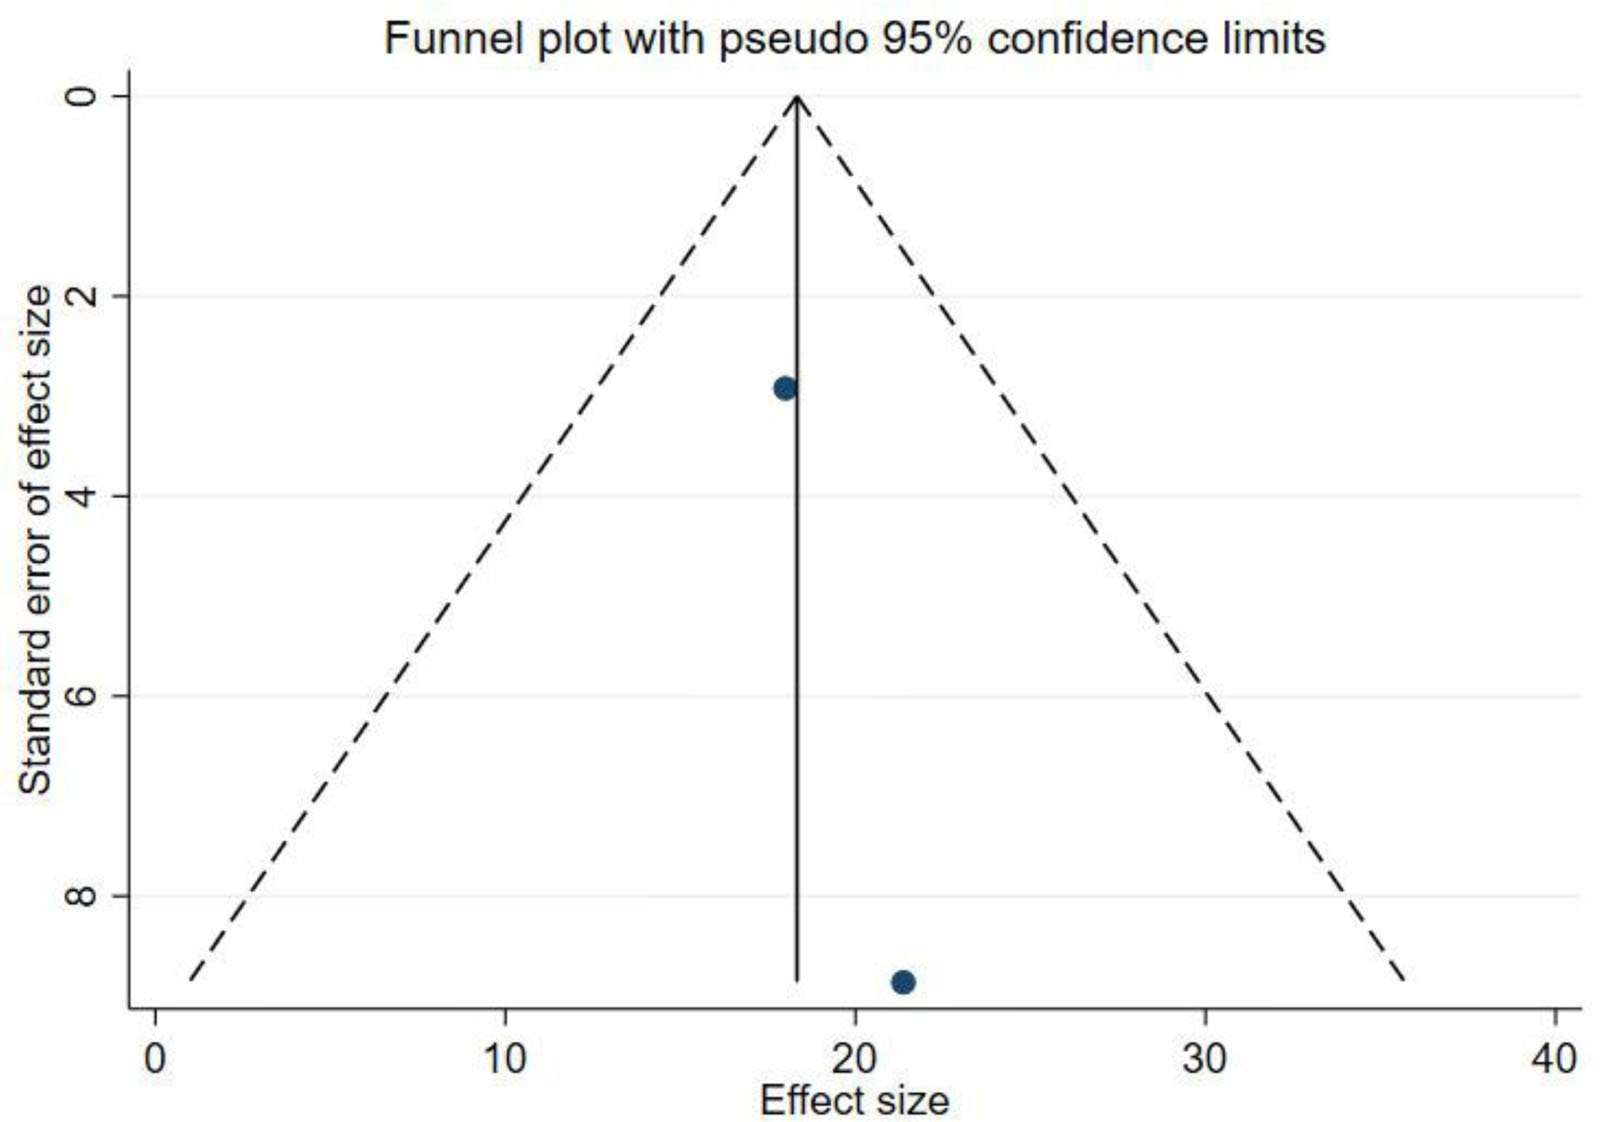

出版偏見:對(duì)納入研究進(jìn)行了發(fā)表偏倚分析,漏斗圖顯示W(wǎng)OMAC不對(duì)稱,而KLS對(duì)稱,提示W(wǎng)OMAC結(jié)果可能存在發(fā)表偏倚(圖4、圖5),因此進(jìn)行了Egger檢驗(yàn),結(jié)果顯示P=0.583,提示不存在發(fā)表偏倚(圖6)。

KLS=膝關(guān)節(jié)Lysholm評(píng)分。